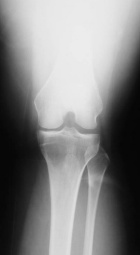

23 year old female with pain in left knee for three months

Zoom image: Radiological image Radiological image.